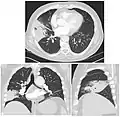

On a posterioanterior and lateral chest radiograph, an entire lobe will be radiopaque, which is indicative of lobar pneumonia.[5]